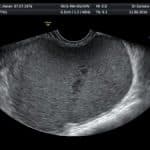

ניתן לחשוד בתופעה זו כאשר מופיעים הסימפטומים שתוארו לעיל. סיפור משפחתי אצל האם או אחות עשויים לסייע. בבדיקה גינקולוגית ומישוש אברי האגן ניתן לזהות רגישות ניכרת, ציסטה שחלתית- אנדומטריומה או מוקדים עמוקים. העדר ממצאים בבדיקה גינקולוגית או בדיקת אולטראסאונד אינם שוללים אנדומטריוזיס. יש צורך בניסיון ומיומנות על מנת למשש מוקדים עמוקים. בדיקת אולטראסאונד הנעשית עי מומחה בתחום עשוייה לסייע במיקום מוקדים עמוקים ומעורבות איברים נוספים. על סמך הכרת כלל התלונות וממצרי הבדיקה ניתן לקבל מושג על מידת המעורבות והחומרה אך על מנת להגיע לאבחנה מלאה יש לבצע ניתוח הקרוי לפרוסקופיה (החדרת סיב אופטי דרך חתך זעיר בבטן לבדיקת אברי הבטן והאגן). בגישה זו ניתן לראות את המיקום, הגודל, ואת מספר המוקדים הקיימים ניתן לקחת ביופסיה על מנת לאשר את האבחנה. מומלץ כי פעולה זו תבוצע עי מומחה לאנדומטריוזיס בעל ניסיון.

הרקמה הנורמאלית בתוך הרחם נקראת רירית רחם או אנדומטריום. כאשר רקמה הדומה לרירית הרחם גדלה מחוץ לרחם המצב נקרא אנדומטריוזיס. האזורים הנפוצים ביותר לגדילה של רקמת אנדומטריום מחוץ לרחם הם איברי הרבייה: שחלות, חצוצרות, ורחם. אחד המקומות הנפוצים ביותר הינן השחלות בהן מופיעה ציסטה שחלתית אנדומטריומה, רקמת אנדומטריום יכולה להופיע גם באיברים נוספים שנמצאים בקרבה אנטומית לאברי הרבייה כגון: שלפוחית השתן, המעי הגס והרקטום. לעיתים נדירות ניתן למצוא רקמת רירית אקטופית אפילו במקומות מרוחקים כגון ריאות ומח.

רקמת רירית הרחם מגיבה לשינויים הורמונליים שמופיעים במהלך המחזור החודשי. גם רקמת רירית הרחם שנמצאת מחוץ לרחם מגיבה לשינויים הורמונליים אלו.  כאשר רקמה זו תדמם באיזור בו היא ממוקמת היא יכולה לגרום להיווצרות הידבקויות לאיברים סמוכים, ציסטות (חללים מלאים בנוזל חום שוקולדי ) הנקראת אנדומטריומה ורקמת צלקת מסביב למוקדים. למע החיסונית תפקיד חשוב ביצירת המחלה.